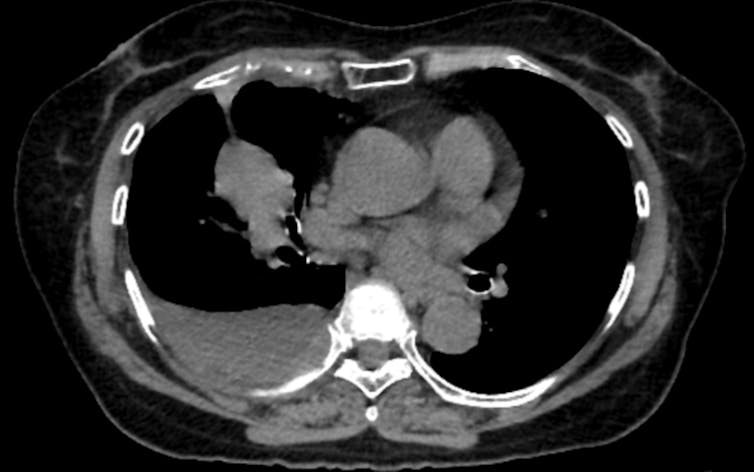

Coronary artery calcium, or CAC, is probably the best demonstration of what opportunistic screening can accomplish. When calcium builds up in the walls of the coronary arteries, it reflects underlying atherosclerosis, the disease process behind most heart attacks. CAC scoring is one of the strongest predictors of future heart attacks, and it adds predictive information beyond what traditional risk calculators provide.

Dedicated cardiac CT scans can measure this calcium precisely. So can a standard lung cancer screening CT, if someone takes the time to look. Studies have found that calcium measurements from lung screening CTs agree closely with those from dedicated cardiac scans, meaning the information is there even when the scan was not designed for cardiac evaluation.

That overlap matters because roughly 19 million noncardiac chest CTs are performed each year in the United States. Every one of those scans passes through the heart. The presence of calcium is visible in the images – yet studies find that when CAC is present, radiologists report it in fewer than half of cases.

A single cross-sectional image from a chest CT shows a mass in the patient’s right lung and fluid surrounding the lung.